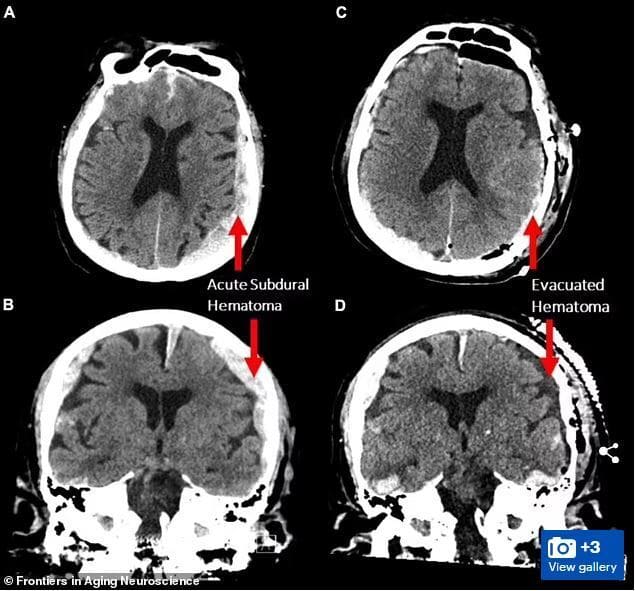

"죽기 직전 지난 삶 주마등처럼 지나간다" 사실

죽기 직전 지난 삶의 중요한 순간들이 주마등처럼 머리 속을 스쳐 지나간다는 말이 사실일 수 있음을 시사하는 과학적 증거가 우연히 포착됐다고 BBC가 23일(현지시간) 보도했다. 한 과학자 팀이 뇌전증(간질)에 걸린 87세 환자의 뇌파를 측정하던 도중 이 환자가 예상치 못하게 심장마비를 일으켜 사망하면서 그의 뇌파가 약 30초 가량 꿈을 꾸거나 기억을 떠올리는 것과 같은 패턴을 따른다는 사실이 밝혀졌다. <사진출처 : 데일리 메일> 2022.2.24